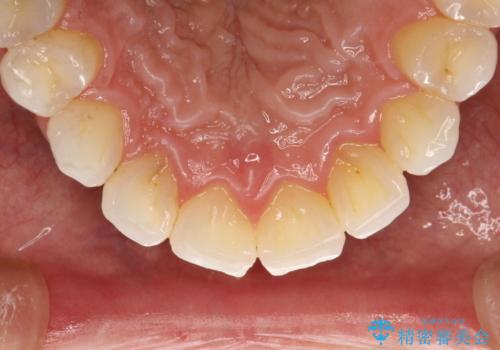

PMTCでお口のメンテナンス

- 痛みや特に気になるところはないが、しっかりとクリーニングしてほしいとのことで来院された患者様です。PMTC 30分コースでのメンテナンスを行いました。

歯を長持ちさせるために、1番の対策が、PMTC を定期的に行うことです。虫歯や歯周病の予防・再発の予防などと、患者様の歯の健康を保つためプロフェッショナルクリーニングを行っています。

痛みや症状が無くても、歯科医院にて専門的なクリーニングを行うことが大切です。